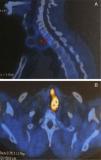

A cintigrafia tiroideia (fig. 2) revelou hiperfixação nodular do terço inferior do lobo esquerdo correspondente a nódulo quente, com restante glândula hipocaptante, consequência de supressão.

A cintigrafia paratiroideia (99mTC sestamibi) revelou, para além do nódulo quente ao nível do lobo esquerdo da tiroide, hipercaptação da paratiroide inferior esquerda (fig. 3), tendo o doente sido submetido a lobectomia esquerda e paratiroidectomia inferior esquerda. A anatomia patológica revelou: